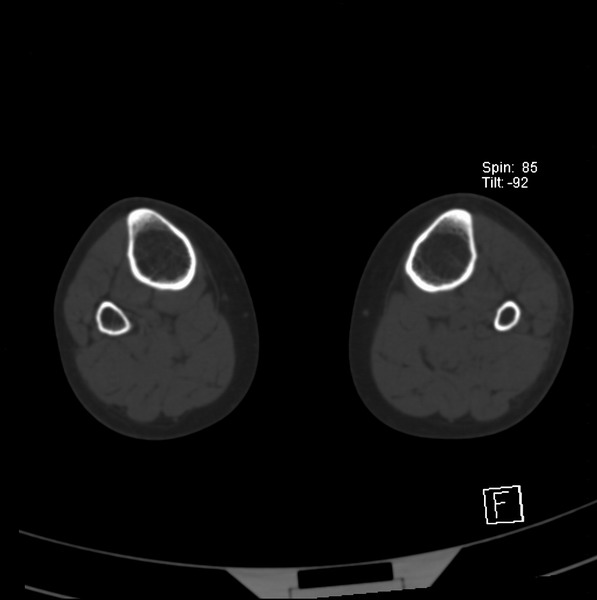

标题: CT21917:右腓骨小头是否骨软骨瘤? [打印本页]

标题: CT21917:右腓骨小头是否骨软骨瘤?

女、43.

不是骨软骨瘤,“牵拽征”,正常变异。有平片吗?

正常变异,“牵拽征”,比目鱼肌牵拽.

比目鱼肌附着点